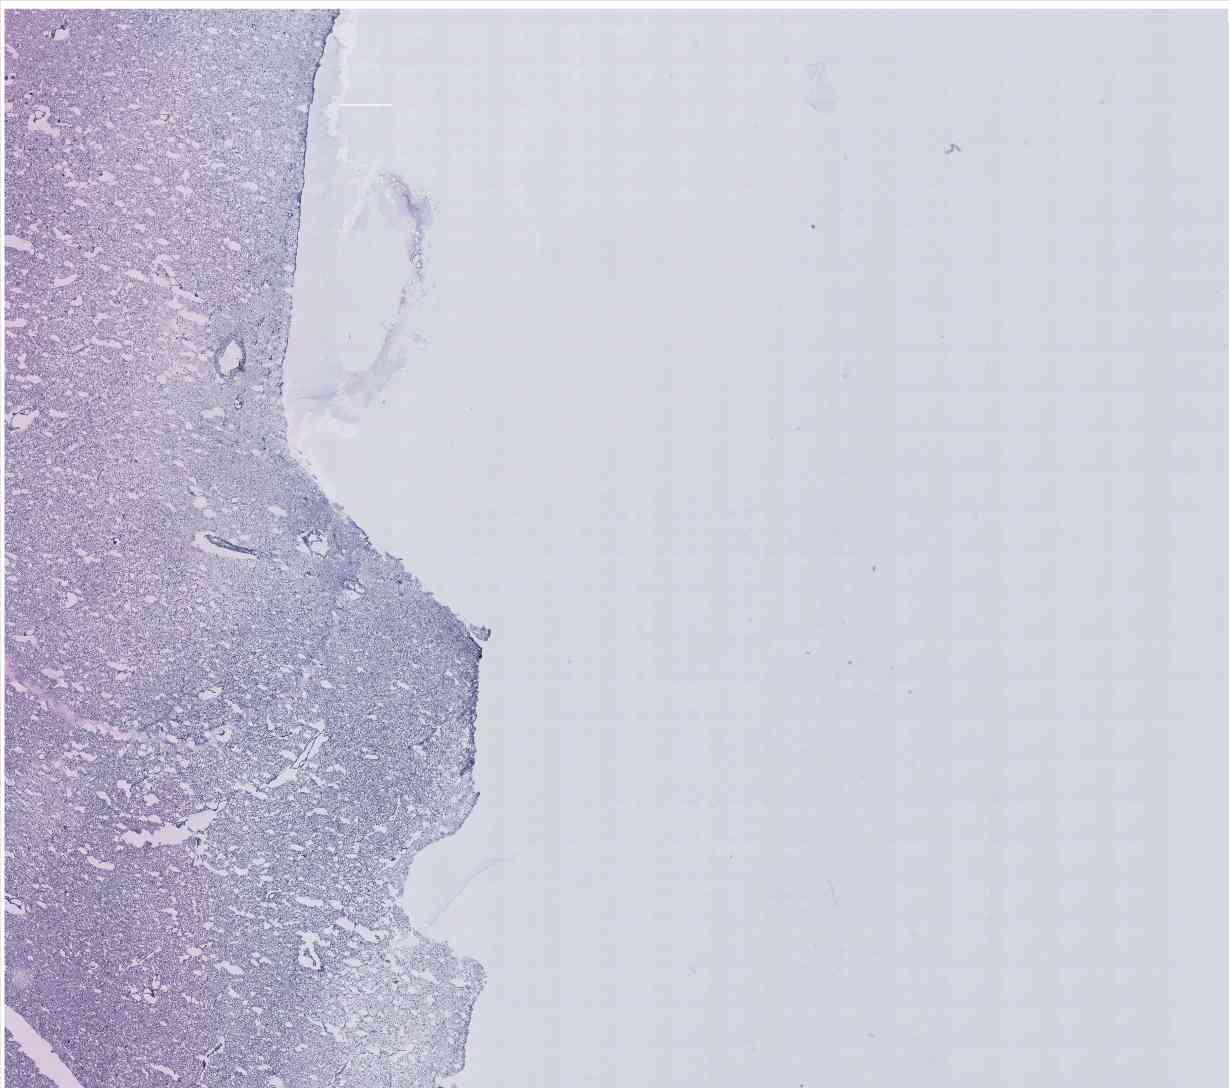

Chip 022 Well D2